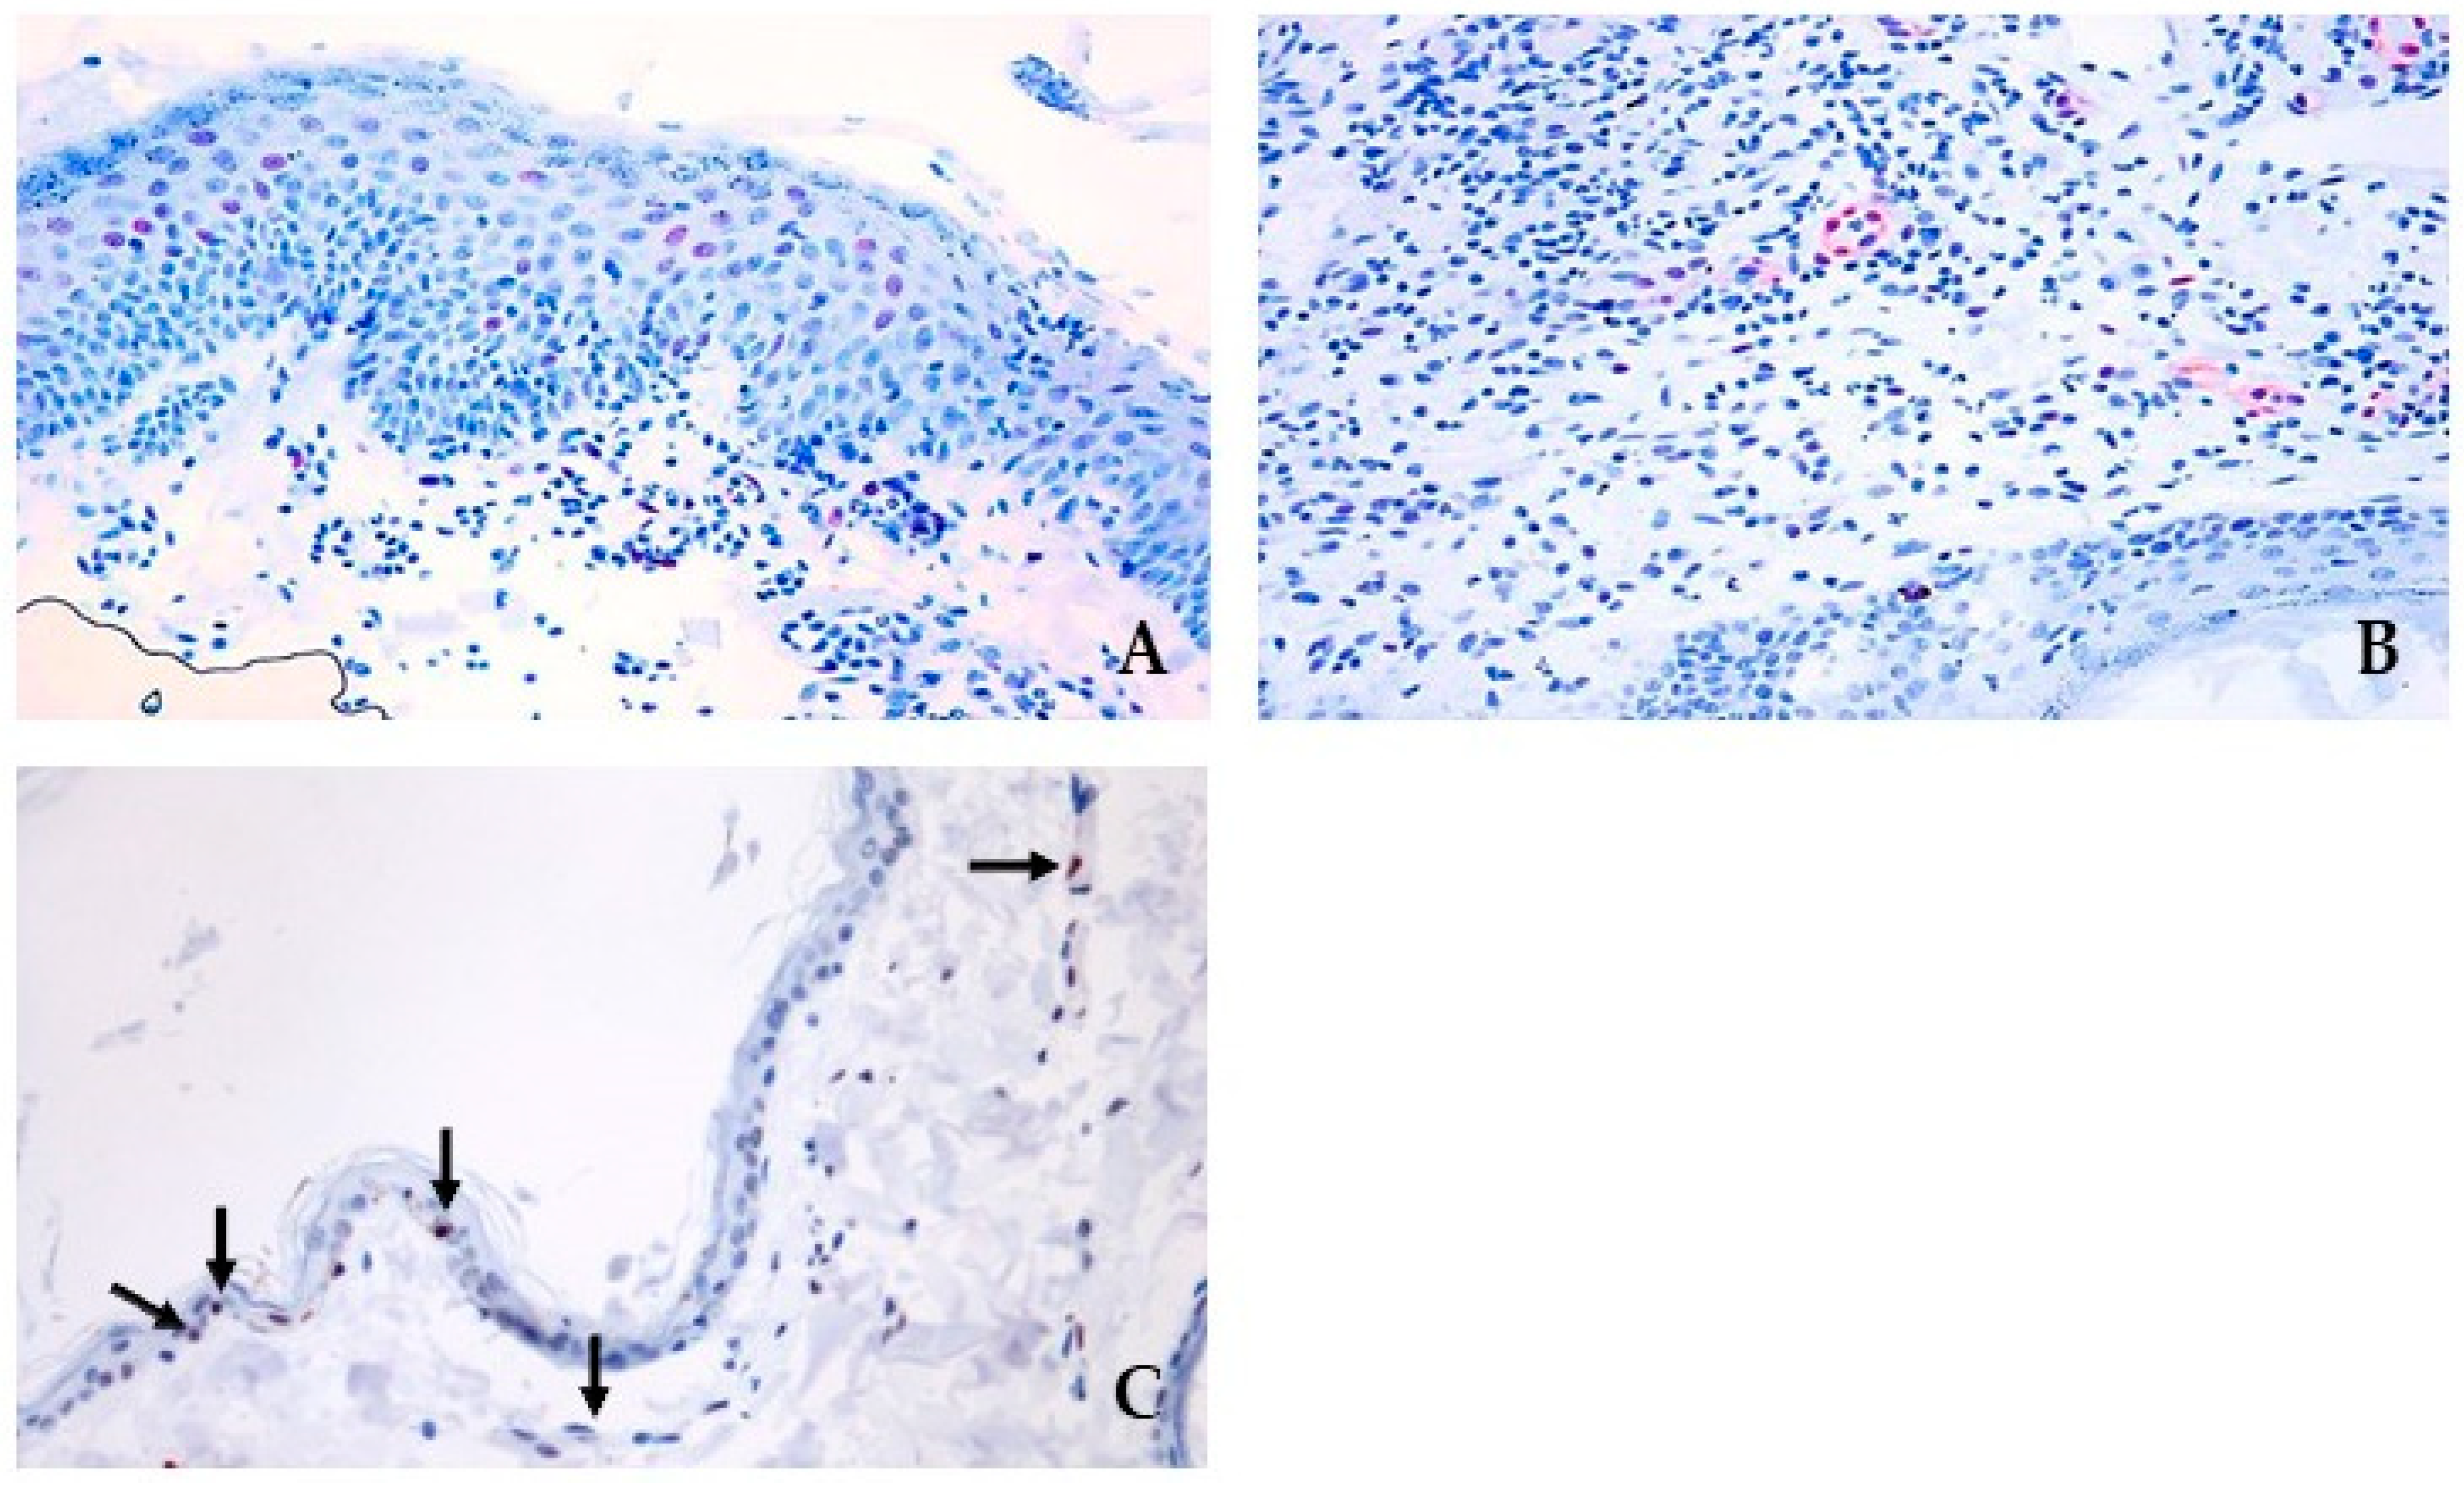

3.3. pSTAT3 and JAK Protein Signalling and Localization